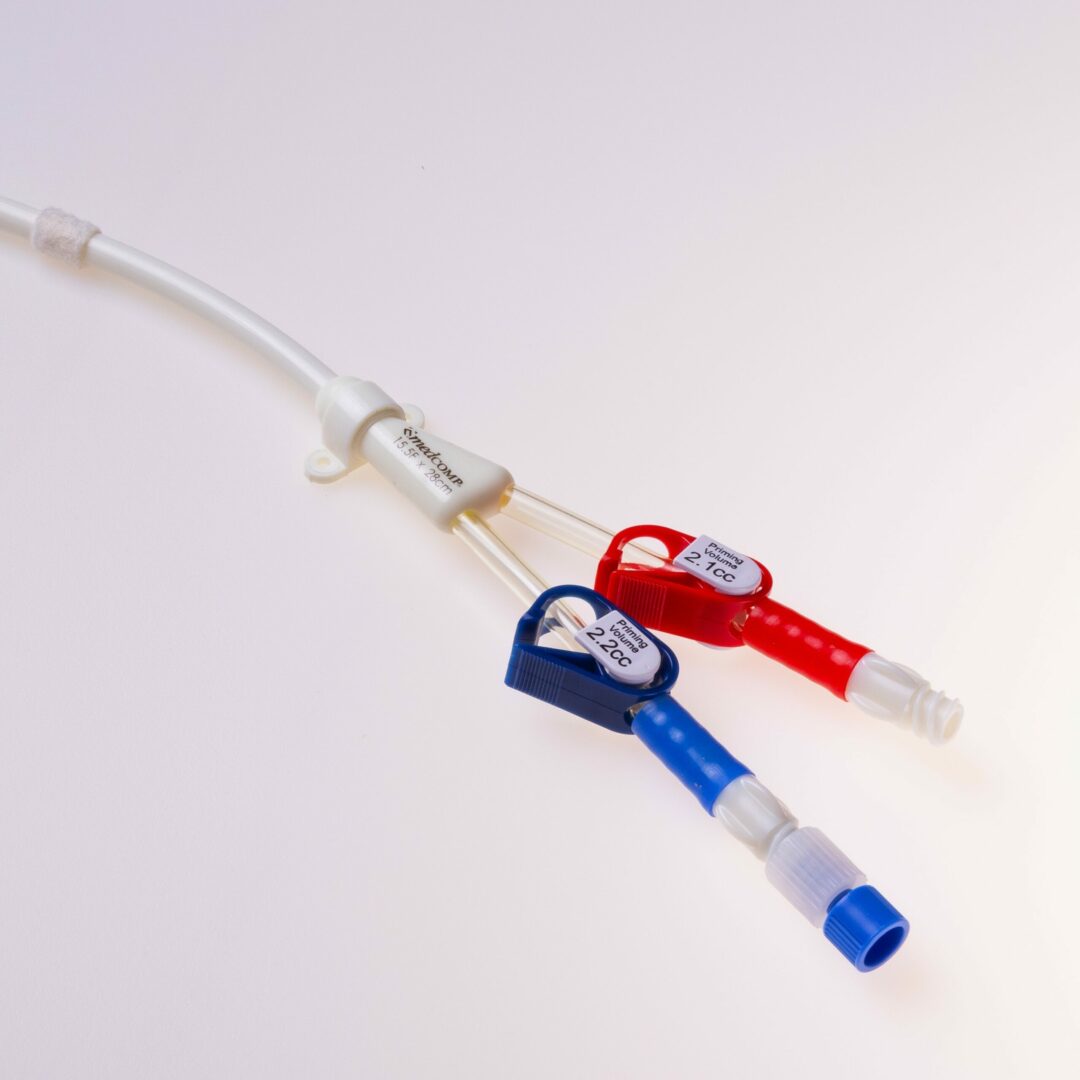

Der THD Titan® ist ein untertunnelter Langzeitdialysekatheter für die chronische Hämodialyse. Er ermöglicht einen mehrjährigen, verlässlichen Gefäßzugang im Dialysebetrieb mit sehr hohen durchschnittlichen Flussraten aufgrund großer Lumina von 15,5 French: die erzielbaren Katheter – Flussraten liegen jenseits von 450 ml / Min.

Der THD Titan® verfügt über ein „Tap Tip“ Spitzendesign.

Der THD Titan® ist ein untertunnelter Vorhofkatheter für die chronische Hämodialyse.

Set Komponenten der E (gerade) und PCE (precurved) Version